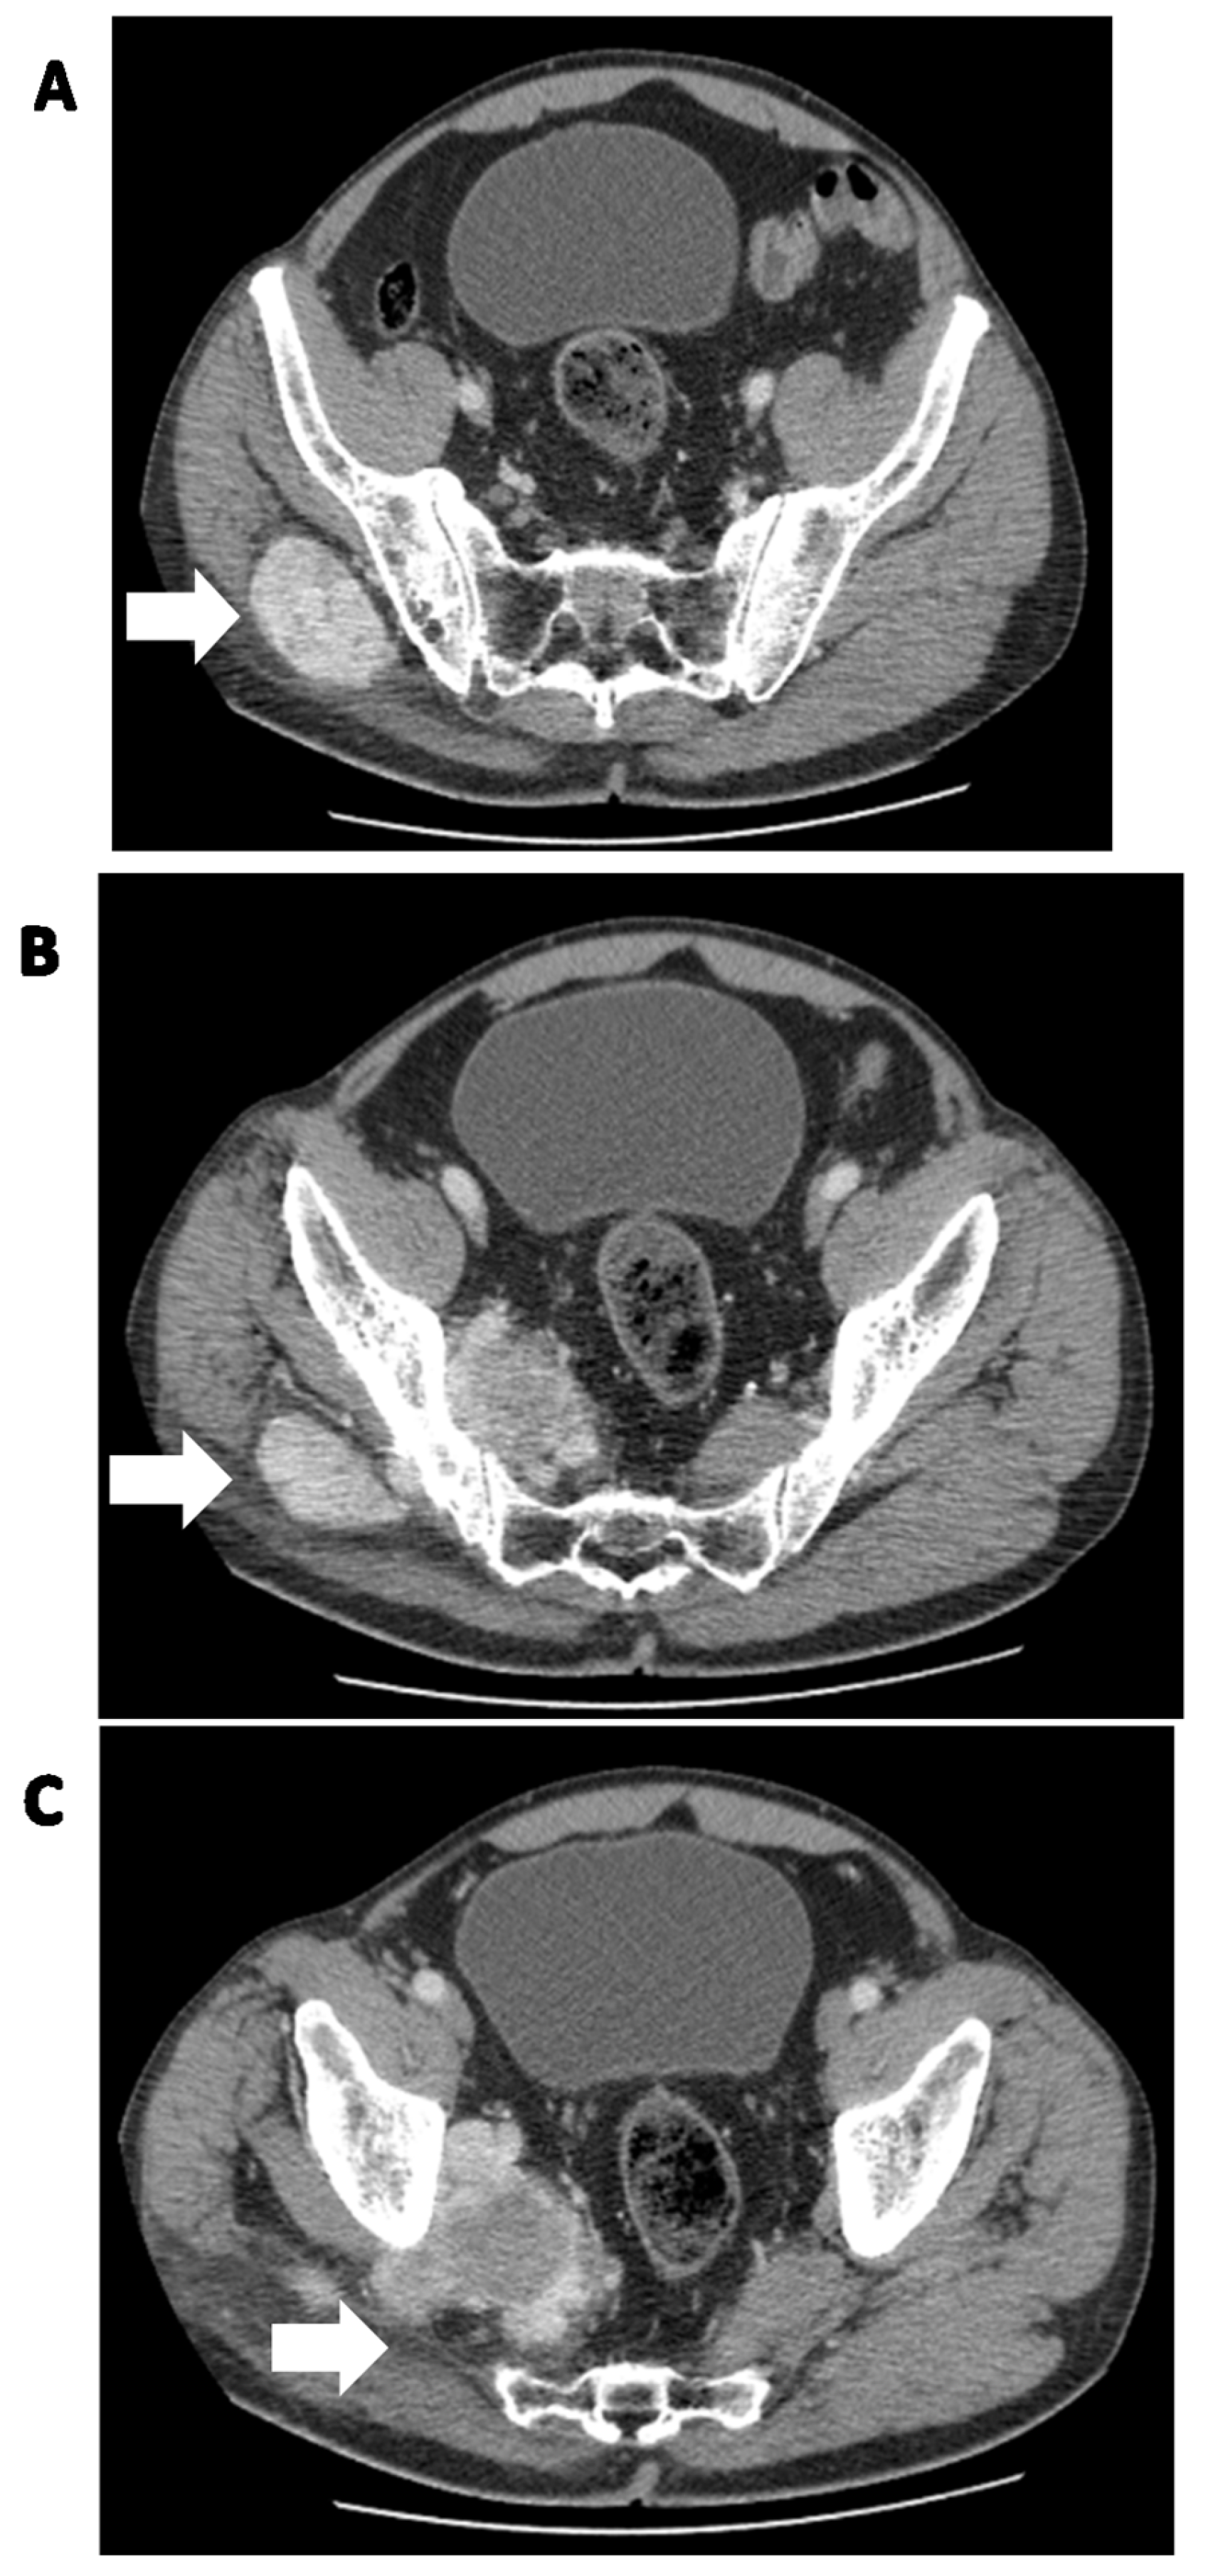

Figure 1.

Solitary fibrous tumor of the pelvic region in a 62-year-old man. (A) Soft tissue mass in the right iliac region (white arrow), (B,C) passing through the pelvic obturator opening into the small pelvis (white arrows).

Figure 2.

Synchronous metastatic lesions in the same patient as in Figure 1. (A) Metastatic lesion (white arrows) with destruction of the C3 vertebra and soft tissue involvement; (B) metastatic liver lesion (white arrow).